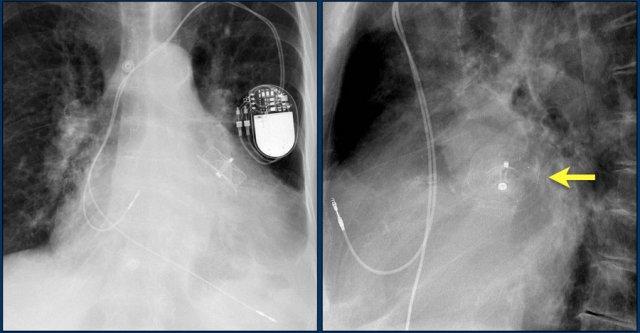

Đây là bệnh nhân có ICD với một điện cực và hai cuộn sốc điện.

Có thể thấy điện cực lưu lại của máy tạo nhịp cũ đã được tháo bỏ.

Nhiều bệnh nhân có điện cực máy tạo nhịp nội tâm mạc được để lại sau khi tháo bộ phát xung.

Tính an toàn của MRI ở bệnh nhân có điện cực máy tạo nhịp nội tâm mạc lưu lại cho đến nay vẫn chưa được nghiên cứu một cách hệ thống.

Tuy nhiên, do nguy cơ tiềm ẩn khi các điện cực này có thể hoạt động như “ăng-ten” gây nóng đáng kể – không khuyến cáo chụp MRI cho những bệnh nhân này (tài liệu tham khảo).